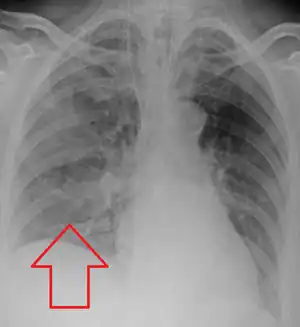

Evaluation of aspiration is generally performed with a video fluoroscopic swallowing study involving radiologic evaluation of the swallowing mechanism via challenges with liquid and solid food consistencies. These studies allow for evaluation of penetration to the vocal folds and below but are not a sensitive and specific marker for aspiration.[15] Additionally, it is difficult to distinguish between aspiration pneumonia and aspiration pneumonitis.[16]

Aspiration pneumonia is typically diagnosed by a combination of clinical circumstances (people with risk factors for aspiration) and radiologic findings (an infiltrate in the proper location).[2] A chest x-ray is typically performed in cases where any pneumonia is suspected, including aspiration pneumonia.[17] Findings on chest x-ray supportive of aspiration pneumonia include localized consolidation depending on the patient's position when the aspiration occurred.[18] For example, people that are supine when they aspirate often develop consolidation in the right lower lobe of the lung.[18] Sputum cultures are not used for diagnosing aspiration pneumonia because of the high risk of contamination.[19] Clinical symptoms may also increase suspicion of aspiration pneumonia, including new difficulty breathing and fever after an aspiration event.[6] Likewise, physical exam findings such as altered breath sounds heard in the affected lung fields may also be suggestive of aspiration pneumonia.[6] Some cases of aspiration pneumonia are caused by aspiration of food particles or other particulate substances like pill fragments; these can be diagnosed by pathologists on lung biopsy specimens.[20]